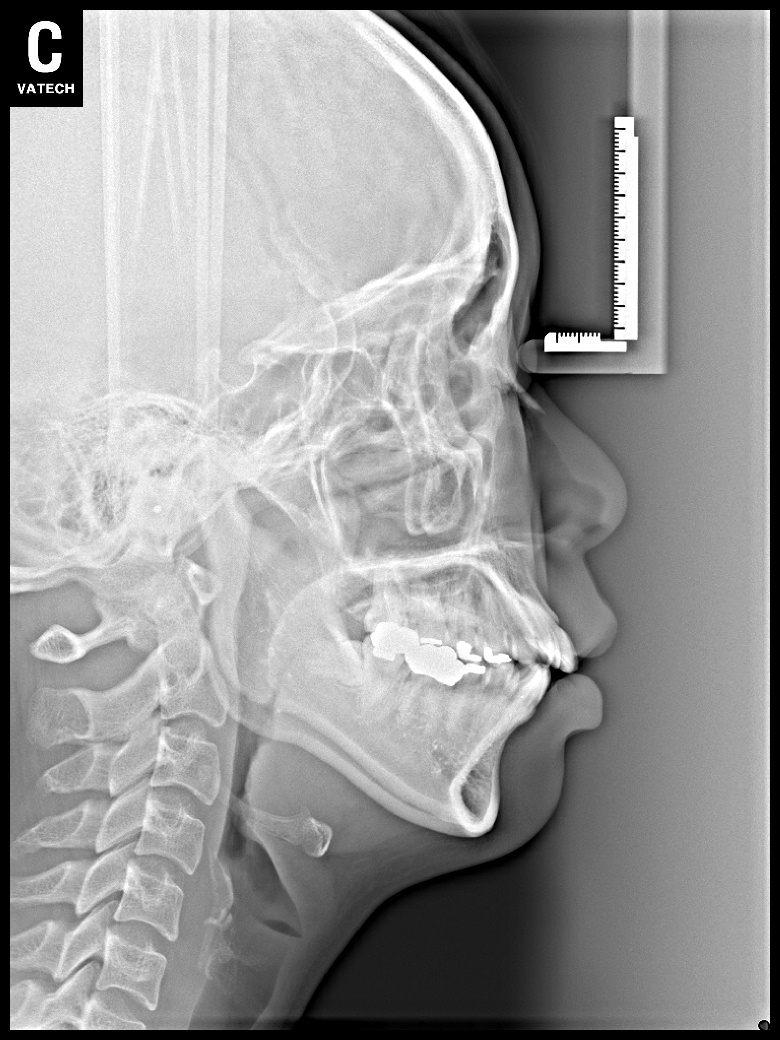

치료 후 사진입니다.